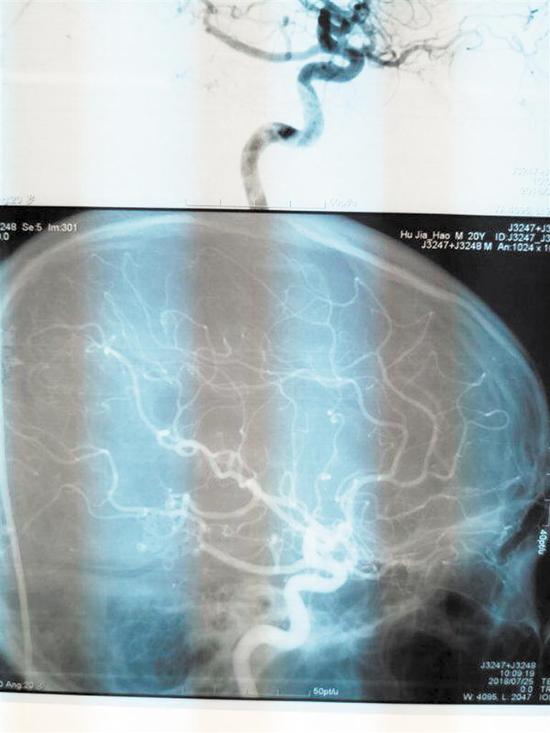

術(shù)后CT圖連續(xù)熬夜誘發(fā)腦出血

為了隨時觀察小陳的情況,陳淳一直在NICU守護著。“此手術(shù)為神經(jīng)外科4級手術(shù),致殘率、死亡率高。手術(shù)后我們一直擔(dān)心會有如癱瘓、失明等后遺癥出現(xiàn),幸運的是,小陳第二天就蘇醒了,神志清醒,無后遺癥出現(xiàn)。復(fù)查DSA,他的畸形血管團全切,恢復(fù)情況良好。”陳淳說。